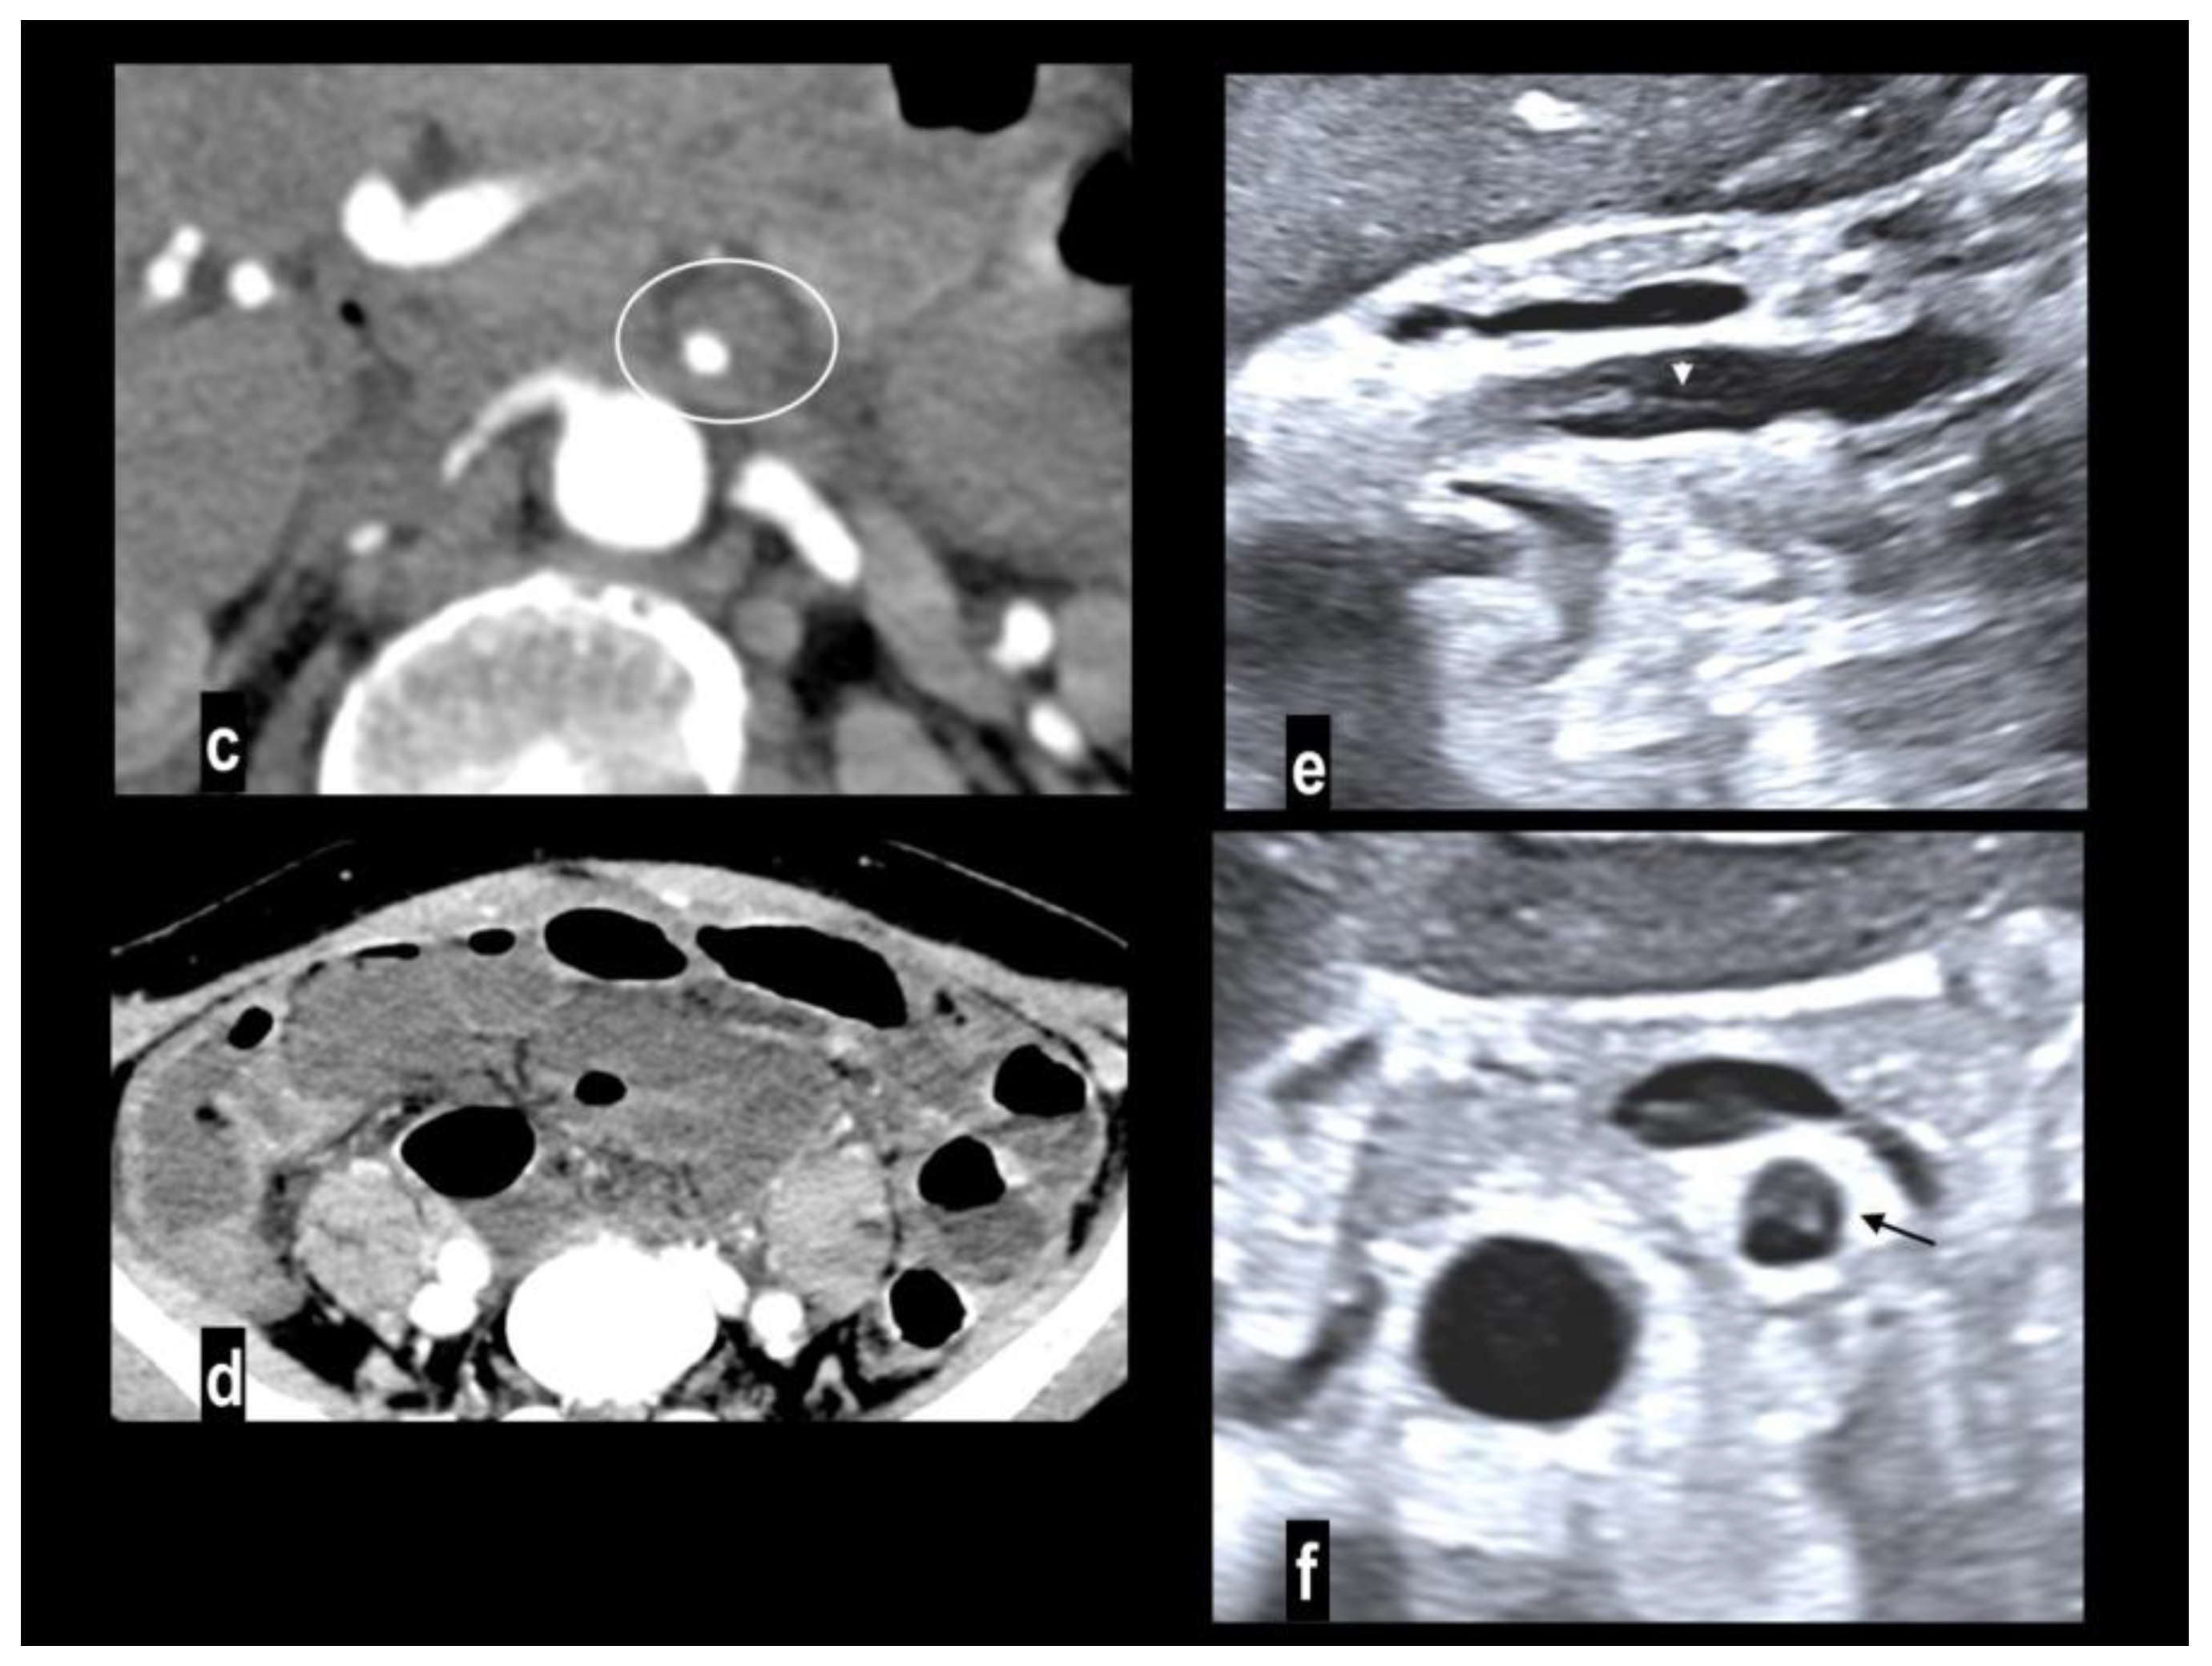

Figure 5. SMA dissection in a 42-year-old woman. MIP arterial images (Figure 5a-b) showed segmentary false lumen thrombosis in the proximal convex side of SMA, with lumen narrowing (arrow). The vessel caliber had increased (Figure 5c, oval). Distally the intimal flap continued in a complete vessel thrombosis (arrowhead), determining bowel ischemia with hypoenhancing paper-thin bowel walls (Figure 5d). Proximal false lumen thrombosis (arrow) and intimal flap (arrowhead) were also well depicted at ultrasound examination performed before MDCT (Figure 5e-f). The patient underwent surgical resection of necrotic loops.